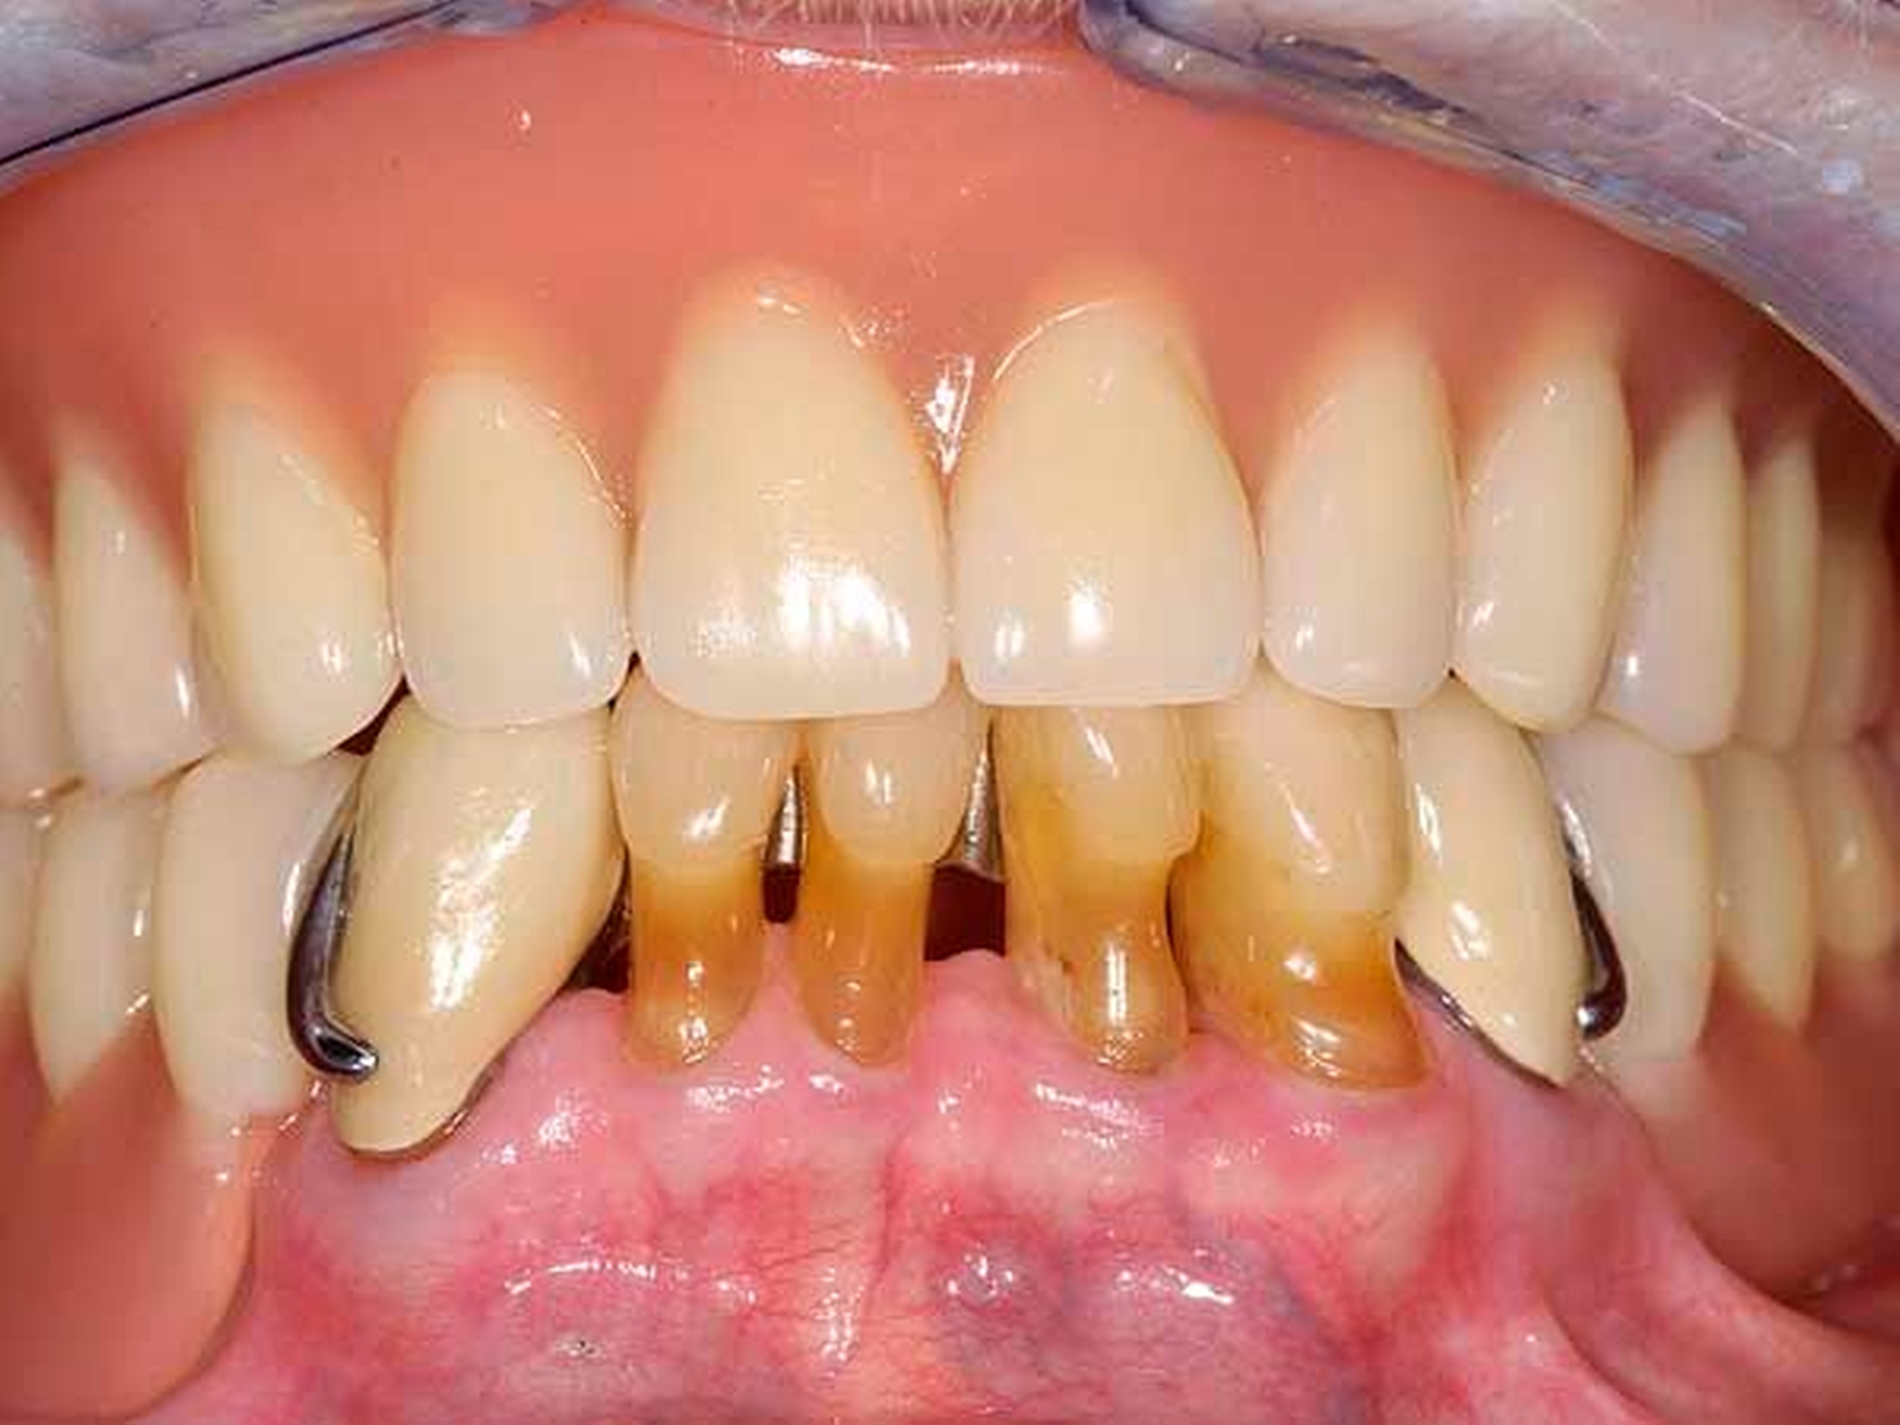

Im Oberkiefer gestattete die Lückengebisstopografie festsitzenden Zahnersatz gemäß den Richtlinien der gesetzlichen Krankenkassen. Im Unterkiefer verblieb nach Extraktion ein karies- und füllungsfreies anteriores Restgebiss von 34 nach 45 (Abbildung 2). Versorgungen mit implantatgestütztem Zahnersatz oder kombiniert festsitzend-herausnehmbarem Zahnersatz schieden aus Kostengründen aus. Angesichts der normalerweise sichtbaren Gussklammer-Verankerungen an den Prämolaren fürchtete die junge Frau eine Demaskierung als Prothesenträgerin.

Die Patientin konnte mit einer Modellgussprothese und zwei RPI-Klammern an den Zähnen 34 und 45 erfolgreich versorgt werden (Abbildungen 3 und 4). RPI steht für Rest (meist sattelferne Abstützung), Proximal Plate (approximale Führungsfläche), l-bar (i-förmiger Retentionsteil). Das RPI-Klammersystem wurde 1963 von Kratochvil [Kratochvil, 1963] eingeführt und von Krol 1973 [Krol, 1973] weiterentwickelt. Das Klammersystem ist kein Exot. Es findet sich in nahezu allen internationalen Standardlehrbüchern der Prothetik und gilt als das mit am besten bewährte Klammersystem für die bilaterale Freiendsituation [Davenport et al., 1992; Krol, 1999; Carr et al., 2000].

Die proximale Platte der RPI-Klammer blockiert wirkungsvoll dislozierende Sattelbewegungen (Abbildung 5), der von gingival inserierende Retentionsarm ist nahezu unsichtbar. Aufgrund des langen Federweges ist der Retentionsarm praktisch ermüdungsfrei und lässt sich gegebenenfalls leicht aktivieren. Die Abstützung liegt sattelfern analog einer Back-Action-Klammer. Für die RPI-Klammer wird am Ankerzahn neben der üblichen mesialen Klammerauflage die disto-approximale Wand parallel zur Einschubrichtung im Schmelz präpariert (Abbildung 6). Die Präparation sollte mindestens 1 mm oberhalb der Papille enden. Die präparierte Fläche dient der flächigen Anlage der proximalen Platte (Abbildung 3).